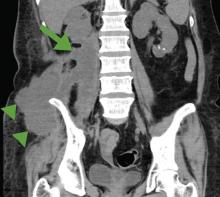

A cancer patient receiving corticosteroids for a brain metastasis developed emphysematous cystitis and psoas muscle abscess.

The patient was admitted to the hospital for percutaneous drainage, which produced 26 mL of pus on the first day and 320 mL on the next day; culture was positive for Escherichia coli. Urine culture was also positive for E coli; blood culture was not. We concluded that these results were secondary to pyelonephritis.

Inflammatory markers such as erythrocyte sedimentation rate and C-reactive protein may be elevated in all patients with iliopsoas abscess, so if those markers are not elevated, we may have to consider other conditions such as cancer.1 Computed tomography is nearly 100% sensitive for iliopsoas abscess and is the gold standard for diagnosis.3

The average size of the abscess is 6 cm. Percutaneous drainage is required if the mass is larger than 3.5 cm.1